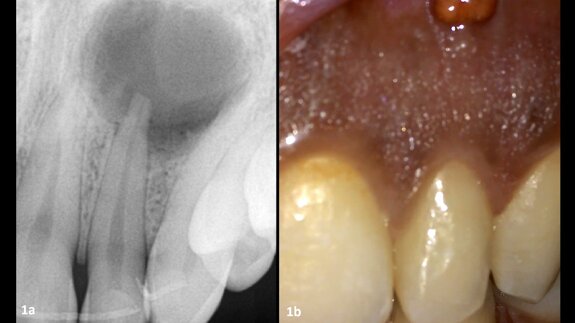

The male patient was a former smoker and 51 years old when the treatment was initiated. He presented with high blood pressure and took Tahor (Pfizer) on a daily basis. In addition, he had been on Kardegic (Sanofi) therapy since a heart attack in 2005. For functional and aesthetic reasons, he wanted a fixed prosthesis in his maxillary arch (Figs. 1a & b).

embedImagecenter("Imagecenter_1_1419",1419, "large");